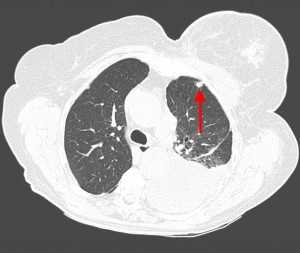

КТ-признаки ТЭЛА. На КТ-ангиограмме, выполненной 53-летнему пациенту, визуализируется внутрипросветный дефект наполнения; имеет место окклюзия артерии переднего базального сегмента нижней доли правого легкого. Определяются также признаки инфаркта правого легкого в виде участка консолидации треугольной формы, широким основанием обращенного к плевре (бугорок Хэмптона).

Патологические изменения на рентгенограммах органов грудной клетки обнаруживаются в большинстве случаев ТЭЛА, однако не являются специфическими. Наиболее часто определяющиеся на рентгенограммах патологические изменения включают в себя ателектаз (спадение) части легкого, плевральный выпот, снижение прозрачности легочной ткани, а также высокое стояние правого или левого купола диафрагмы. Классическими рентгеновскими признаками инфаркта легкого является наличие затемнения клиновидной (треугольной) формы, широким основанием обращенного к плевре, верхушка которого направлена к корню легкого (бугорок Хэмптона), либо уменьшение выраженности сосудистого легочного рисунка в зоне тромбоэмболии (симптом Вестермарка).